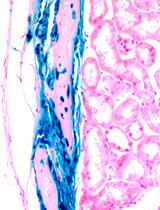

小鼠妊娠期 β 细胞质量的评估

The Assessment of Beta Cell Mass during Gestational Life in the Mouse

YK Yury Kryvalap

JC Jan Czyzyk

1453 Views

Mar 20, 2023

Successful advancement in the treatment of diabetes mellitus is not possible without well-established methodology for beta cell mass calculation. Here, we offer the protocol to assess beta cell mass during embryonic development in the mouse. The described protocol has detailed steps on how to process extremely small embryonic pancreatic tissue, cut it on the cryostat, and stain tissue slides for microscopic analysis. The method does not require usage of confocal microscopy and takes advantage of enhanced automated image analysis with proprietary as well as open-source software packages.